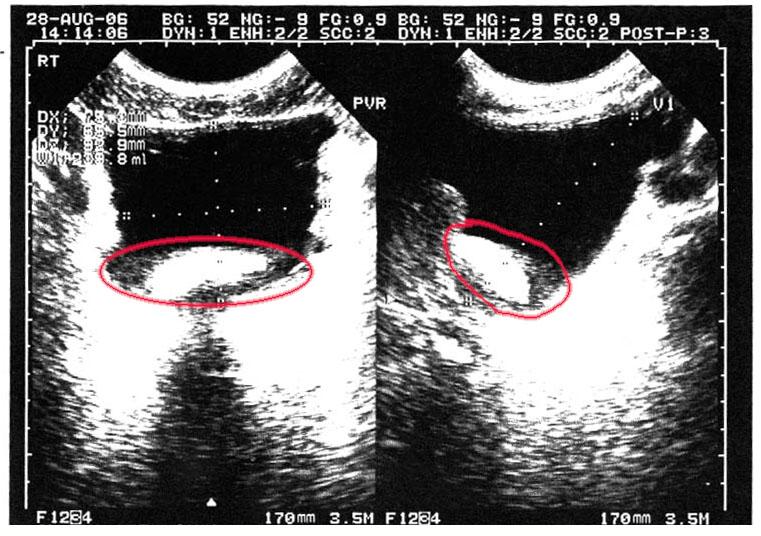

blocking December 27, 2011December 27, 2011 admin Previous Next ultrasound revealing the mass blocking urination